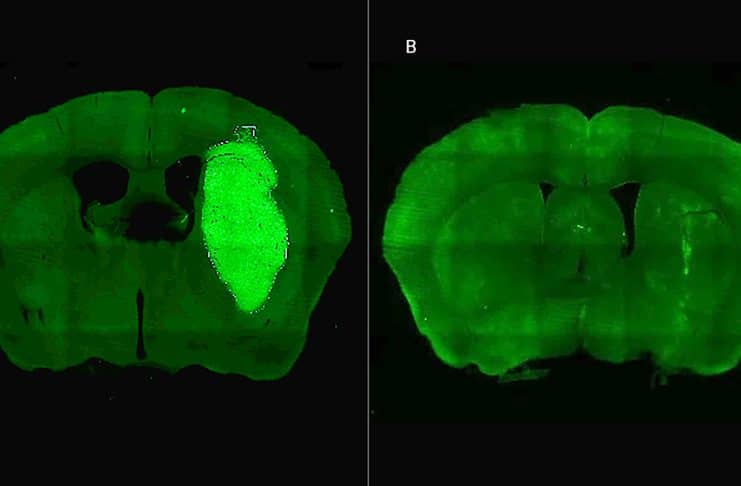

Para evaluar la estrategia, los investigadores emplearon modelos celulares murinos y humanos, incluyendo cultivos derivados de biopsias de pacientes con glioblastoma, desarrollados por Guillermo Videla Richardson del Instituto FLENI. En estudios in vivo realizados en ratones, el equipo de Candolfi, junto con Flavia Zanetti del Instituto de Ciencia y Tecnología César Milstein (CONICET-Fundación Pablo Cassará), diseñó un vector adenoviral que expresa P60 directamente en las células tumorales. “Una sola inyección intratumoral de este vector inhibió el crecimiento del tumor y, combinado con quimioterapia, logró la erradicación del tumor y la sobrevida a largo plazo en un tercio de los ratones tratados”, destaca Candolfi. Además, los tratamientos no mostraron efectos neurotóxicos, lo que sugiere un buen perfil de seguridad.